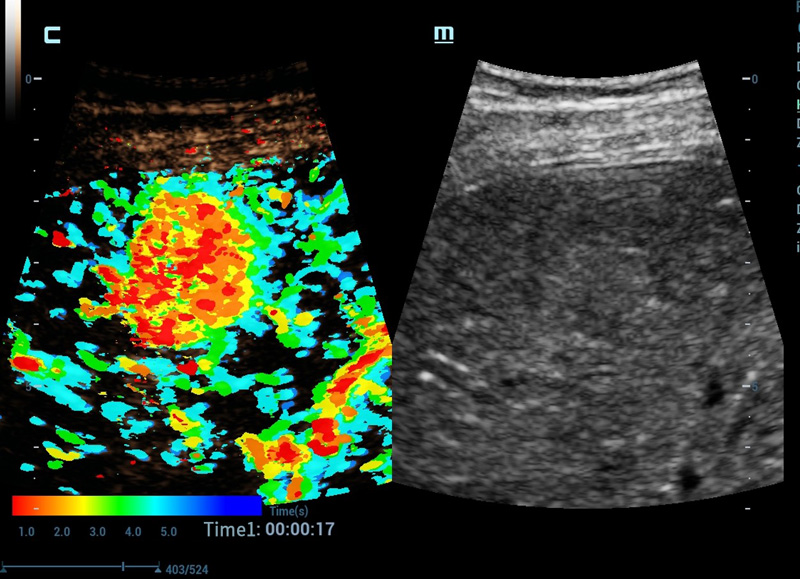

HiFR CEUS

Per ulteriori approfondimenti sulle lesioni

Nuova QA CEUS

Strumenti di quantificazione CEUS all'avanguardia

CEUS Chrono Parametric Mode

CEUS a colori per semplificare la diagnosi

CEUS avanzata

CEUS avanzata